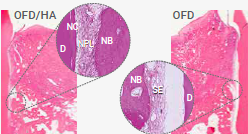

Der Einfluss von Hyaluronsäure auf die knöcherne Regeneration wurde in einem Tierversuch am Modell der Heilung von Extraktionsalveolen untersucht.24

Die zusätzliche Anwesenheit von HA beschleunigte die frühzeitige Neoangiogenese und führte zu einer deutlich verbesserten Knochenqualität, sowohl im apikalen als auch im zentralen Bereich der Alveole.

Eine histologische Begutachtung der Knochenqualität nach 6 Monaten zeigte in der xHyA-Gruppe eine deutlich verbesserte Knochenqualität im Sinne von mehr neu gebildetem Knochen und weniger avitalen Restpartikeln.

Diese Beobachtung wurde auch in einem Split- Mouth Case erhalten, in dem Extraktionsalveolen entweder mit einem langsam resorbierbaren Knochenersatzmaterial (DBBM) alleine oder mit einer Kombination aus DBBM/xHyA aufgefüllt wurden.

Nach 3 Monaten waren in der xHyA-Gruppe deutlich mehr neu gebildeter Knochen und deutlich weniger Restpartikel des avitalen Knochenersatzmaterials vorhanden.27